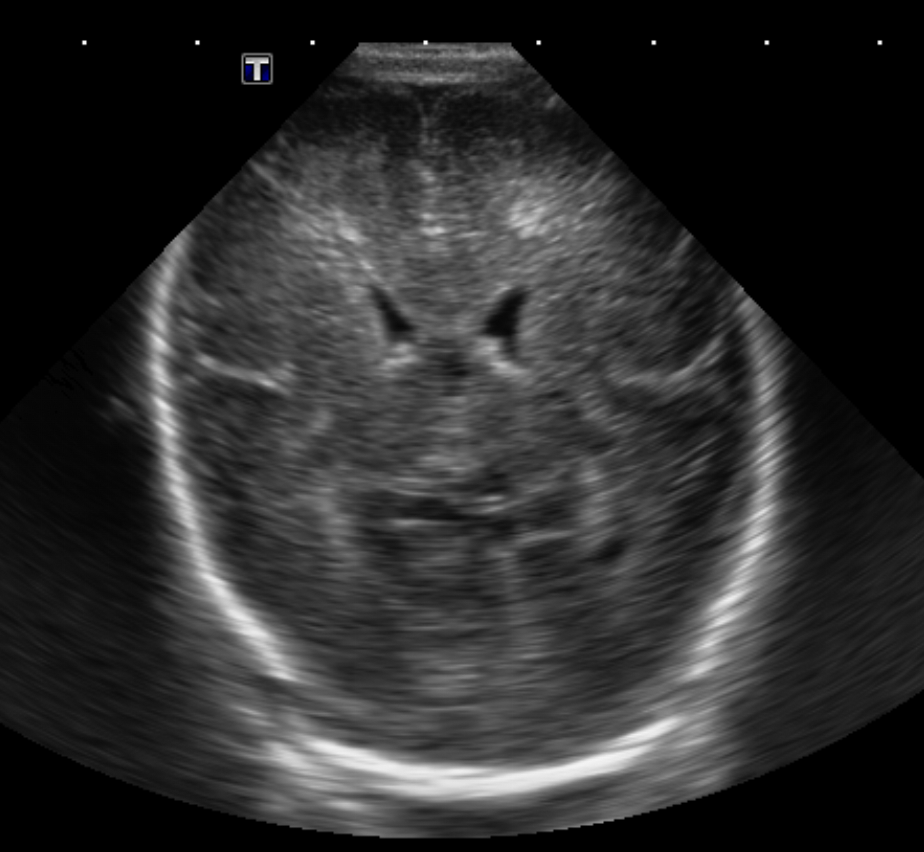

Brain

The brain is immature. [Yes/No]

There is under-sulcation and open sylvian fissures. [Yes/No]

There is/are multiple hypoechoic areas in the periventricular white matter. [Yes/No]

There is/are multiple hyperechoic areas in the periventricular white matter. [Yes/No]

There is diffuse cerebral edema with diffusely increased echogenicity of the brain parenchyma and loss of grey white matter differentiation. [Yes/No]

The thalami/basal ganglia are hypoechoic. [Yes/No]

There is periventricular calcification. [Yes/No]

There is intra-parenchymal calcification. [Yes/No]

Germinal matrix hemorrhage (Only in the premature infants): Please do not answer if the patient is a full term.

There is a germinal matrix hemorrhage, consistent with a grade I hemorrhage. [Yes/No]

There is an intraventricular extension consistent with a grade II hemorrhage. [Yes/No]

There is an intraventricular extension with the dilatation of ventricles, consistent with a grade III hemorrhage. [Yes/No]

There is an intra-parenchymal extension, consistent with grade IV hemorrhage. [Yes/No]

On color Doppler examination, the Resistive index in the anterior cerebral artery is…

There is a loss of the diastolic flow on the Doppler exam. [Yes/No]

There is altered vascularity on Doppler imaging. [Yes/No]

There is an AVM in the region of… [Yes/No]